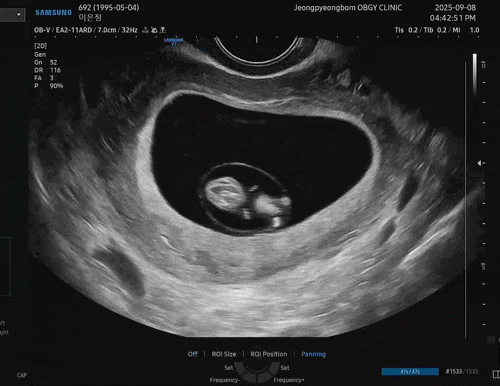

주수일기 10-11주차 : 분만예정일 확정, 다낭성 임산부 태아보험, 임산부 치약 , 두통 타이레놀

안녕하세요 ! 10-11주차 일상을 포스팅 하려고 해요! 이제 10주차라니 1/4정도 왔네요 ... 갈길이 아주 멀...

주수일기 8-9주차 : 젤리곰 확인, 증상

아직까지는 갈 때마다 수주가 3-4일씩 차이 나서 지금이 7주인지 8주인지 정확하게 모르겠는 나... 그냥 내...